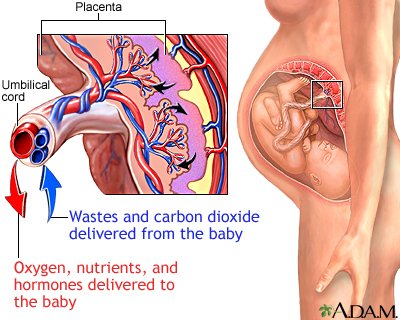

Placenta previa is a problem of pregnancy in which the placenta grows in the lowest part of the womb (uterus) and covers all or part of the opening to the cervix.

The placenta grows during pregnancy and feeds the developing baby. The cervix is the opening to the birth canal.

During pregnancy, the placenta moves as the womb stretches and grows. It is very common for the placenta to be low in the womb in early pregnancy. But as the pregnancy continues, the placenta moves to the top of the womb. By the third trimester, the placenta should be near the top of the womb, so the cervix is open for delivery.